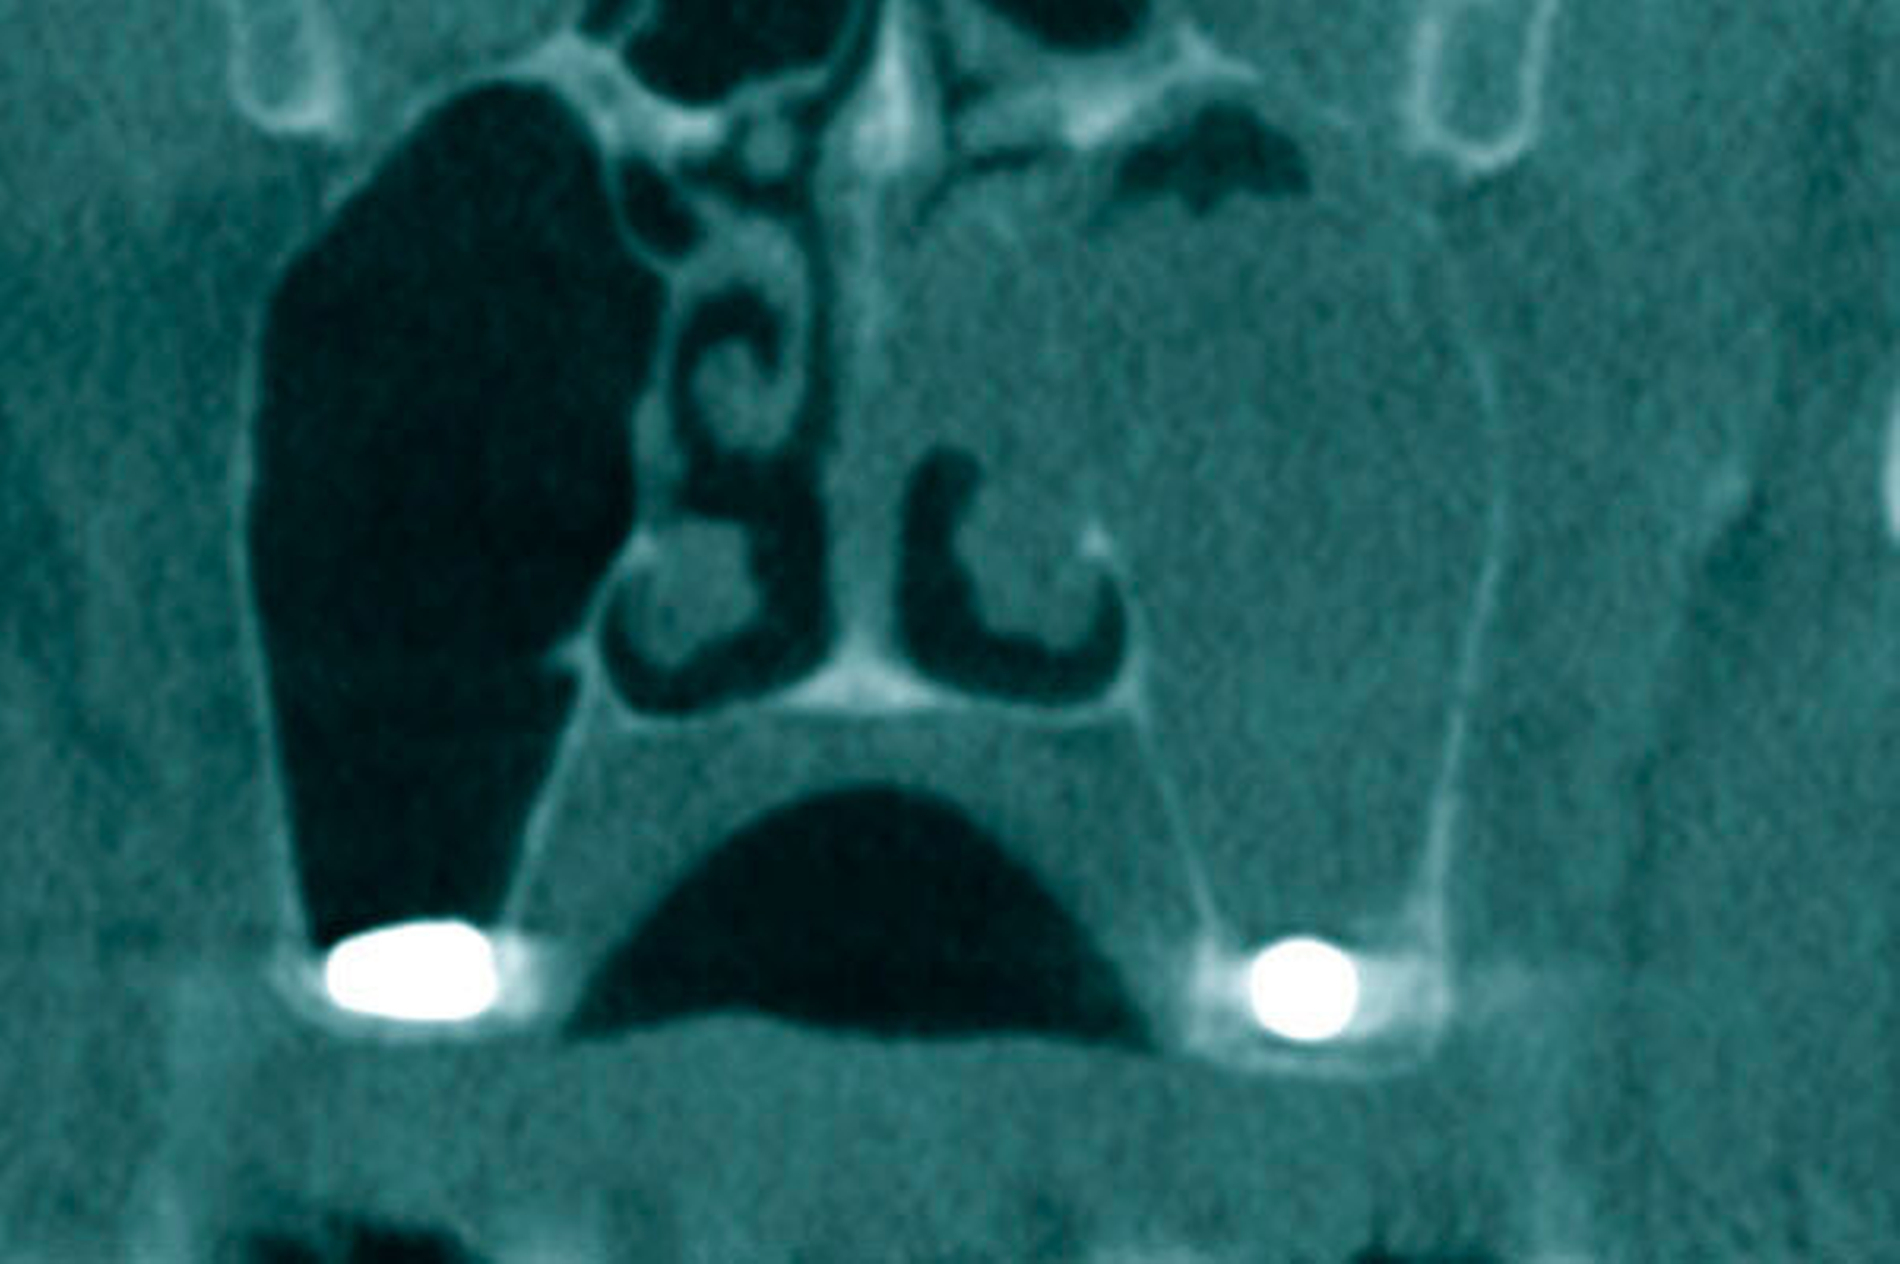

Zur weiteren Diagnostik und zur Beurteilung der Lage des Fremdkörpers wurde eine Digitalen Volumentomografie (DVT) durchgeführt. Diese bestätigte die Verdachtsdiagnose eines dislozierten Implantats im Bereich des Ostium naturale, wobei der Sinus maxillaris selbst Hinweise auf eine basale chronische Sinusitis aufwies (Abbildung 2).

Zur weiteren Diagnostik wurde auch hier eine DVT angefertigt, auf der sich in beiden Kieferhöhlen jeweils ein Implantat identifizieren ließ. Der linke Sinus maxillaris zeigte das Bild einer totalen Kieferhöhlenverschattung bei Verdacht auf Flüssigkeitsansammlung, die rechte Kieferhöhle wies keine Entzündungszeichen auf (Abbildung 6).